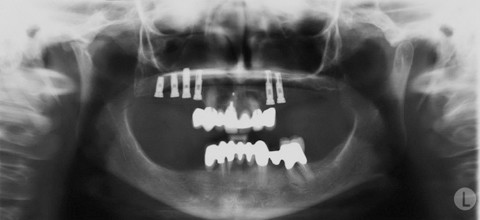

Abb. 1: Externe Rö-Aufnahme vom 31.7.2000: Ausgeprägte knöcherne Atrophie im gesamten distalen Oberund Unterkieferbereich.

Abb. 2: OPD vom 15.11.2000 – OK: Unsere erste einteilige Brücke auf den fünf vorimplantierten Nobel Biocare®-Schrauben sowie auf zwei BOI® im zweiten Quadranten paramedian und lateral-distal.

Abb. 3: Röntgenkontrolle vom 8.5.2001. Im OK: zweiteilige Brückenkonstruktion. UK: einteilige Brücke auf zwei einscheibigen basalen Implantaten und einem zweischeibigen BOI® in der Region des unteren Eckzahns.

Abb. 4: Die vorläufig abschließende OPD-Kontrolle vom 14.5.2008, sieben Jahre nach unserem Eingriff, zeigte eine unverändert gute Situation.